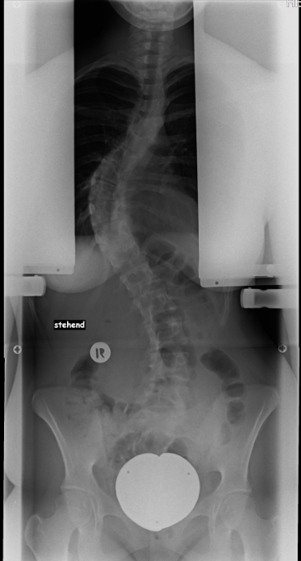

Rechtskonvexe Thorakalskoliose bei einem 15 jährigen Mädchen:

Mit Hilfe einer Wirbelsäulenganzaufnahme, einem Röntgenbild der kompletten Wirbelsäule, können der Krümmungswinkel sowie die Verdrehung der Wirbelkörper gemessen werden. Es sollte immer die gesamte Wirbelsäule auf einer Aufnahme abgebildet und nicht mehrere kleine Bilder angefertigt werden, da man die Krümmung sonst nicht exakt vermessen und die Statik beurteilen kann.

Für diese Wirbelsäulenganzaufnahmen braucht man spezielle, sehr teure Röntgenröhren, die natürlich nicht jeder Arzt hat. Deswegen kann es sein, dass du in ein spezialisiertes Wirbelsäulenzentrum überwiesen wirst. Die Winkel werden in „Gradzahlen nach Cobb“ angegeben, da Dr. Cobb diese Messmethode entwickelt hat. Vor einer Operation werden noch sogenannte Bending-Aufnahmen angefertigt. Du musst dich einmal so weit es geht nach links und dann nach rechts biegen. Danach kann man ausmessen, welche Krümmung schon steif (rigide) ist und welche noch so flexibel ist, dass sie sich noch selbständig ausgleichen kann. Das ist vor allem für die OP-Planung wichtig.